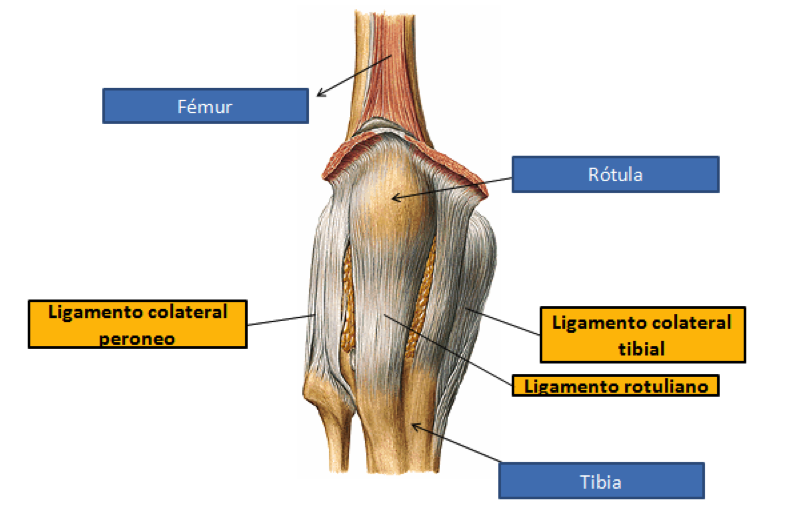

La articulación de la rodilla está asegurada por muchas estructuras ligamentosas (ligamento: tejido conjuntivo que une los huesos entre sí). La función de estos ligamentos es impedir que los huesos que forman la articulación se rocen entre sí con fuerza durante los movimientos y mantienen la estructura. En una visión exterior de la rodilla se pueden observar 3 ligamentos principales: ligamento rotuliano, ligamento colateral peroneo y ligamento colateral tibial.